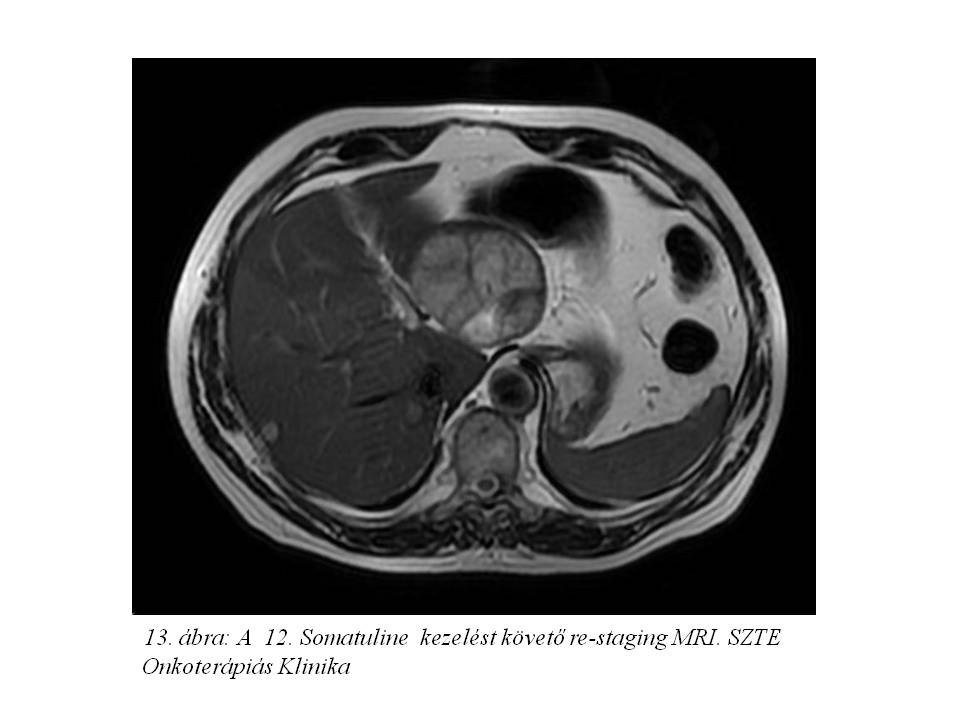

Ezt követően bőrgyógyászati ellátás vált szükségessé testszerte jelentkező viszkető urticaria miatt, felmerült octreotidra való túlérzékenység lehetősége. Emiatt kezelését a továbbiakban lanreotiddal (Somatuline) folytattuk, ugyancsak 4 ciklusonként végzett re-staging mellett. Jelenleg a hasi MR vizsgálaton (11. ábra, 12. ábra, 13. ábra) változatlan status látható, a chromogranin szint emelkedése mellett (266,9 – 310 – 427 ng/ml).